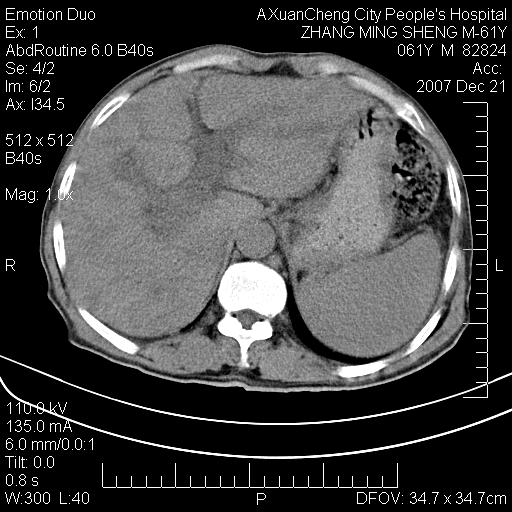

标题: CT11031:M61Y,胰腺占位 [打印本页]

标题: CT11031:M61Y,胰腺占位

大家侃侃门静脉和胆管系统怎么回事,肝内转移?

胰腺癌肝转移

肝硬化,门脉高压,脾肿大;弥漫性肝癌,肝内、门脉、腹膜后淋巴结转移,肝内外胆管扩张,胰头区占位,建议mr检查

胰腺癌伴肝内转移;门脉、肠系膜上v癌栓形成。

考虑为:胰腺癌伴肝脏转移、腹膜后淋巴结转移,门静脉及肠系膜上静脉瘤栓形成。

胰体尾癌伴肝内转移,门静脉及肠系膜上静脉瘤栓形成.

肝硬化,脾大. 胰腺癌伴肝内转移;门脉、肠系膜上v癌栓形成。